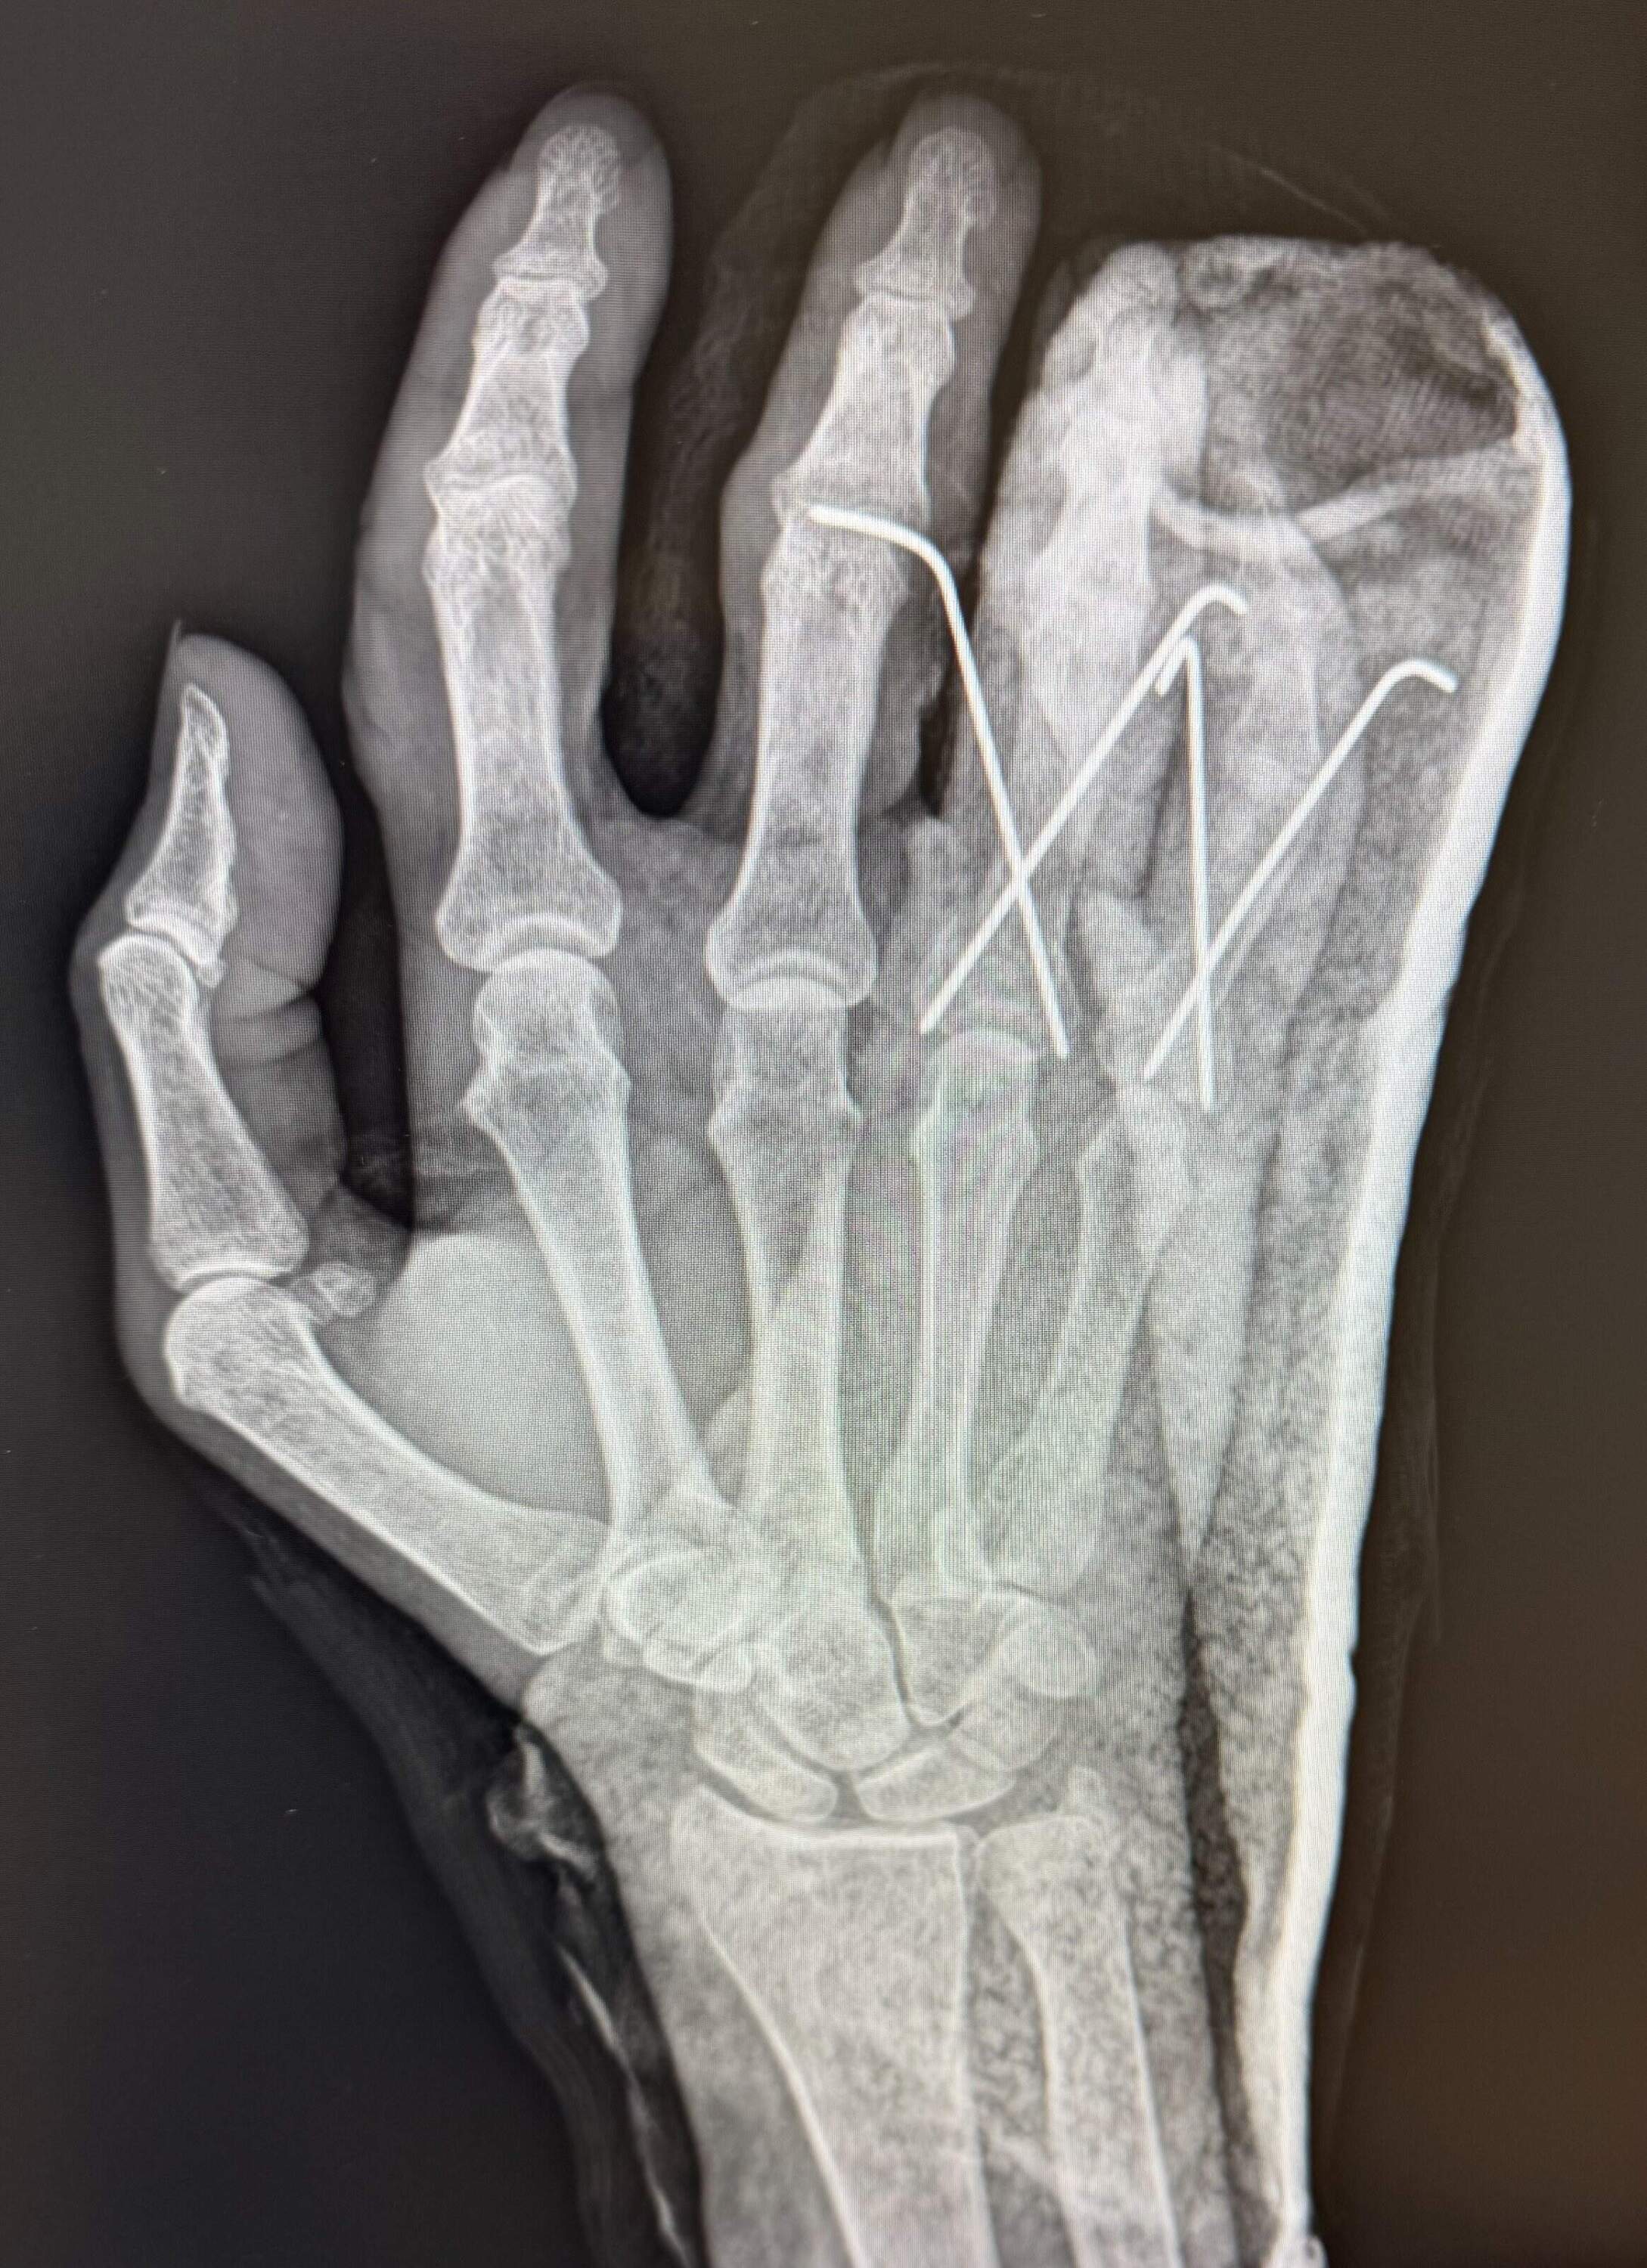

But something hurts; something hurts bad. I roll onto my back and lift my hand in the air. It’s throbbing. Three of my fingers are headed in the wrong direction. My middle finger points off to the left, like a directional heading down a dead end. My ring finger looks like it’s pointing in the opposite direction, my pinky is buckled in the middle, and my knee is screaming. My ribs ache.

An x-ray of the author's right hand, showing two broken finger and a dislocated finger, after she fell on the tennis court. (Courtesy Kathy Gunst)An x-ray of the author’s right hand, showing two broken finger and a dislocated finger, after she fell on the tennis court. (Courtesy Kathy Gunst)

At the ER, they tell me I need surgery, right away. Two fingers broken in several spots. The third finger is dislocated. I also have a broken rib. The ER doctor puts my fingers in a temporary cast (surgery will be days later). I wake to pain and a big fat cast that makes me look like I’m trying out for the role of Captain Hook.